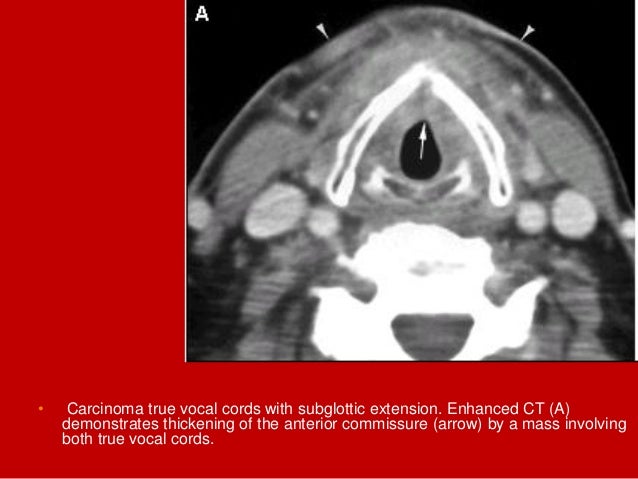

60. 60. • Carcinoma true vocal cords with subglottic extension. Enhanced CT (A) demonstrates thickening of the anterior commissure (arrow) by a mass involving both true vocal cords.

61. 61. • Carcinoma true vocal cords with subglottic extension. Enhanced CT • (B) The mass descends into the subglottic region and perforates the cricothyroid membrane and inferior thyroid cartilage to invade the soft tissues of the neck (black arrowheads). Portions of the mass are hypodense due to necrosis. The airway (asterisk) is markedly narrowed. Prior radiation therapy has caused skin thickening (white arrowheads).